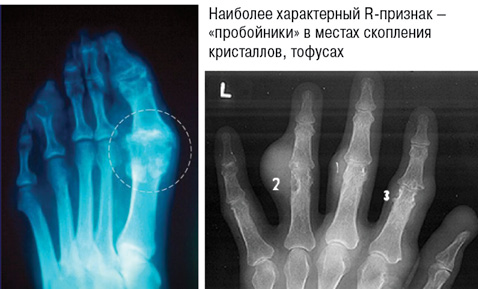

2. Рентгенологические стадии поражения суставов (рис. 7):

• I — крупные кисты (тофусы) в субхондральной кости и в более глубоких слоях, иногда уплотнения мягких тканей;

• II — крупные кисты вблизи сустава и мелкие эрозии суставных поверхностей, постоянное уплотнение околосуставных мягких тканей, иногда — с кальцификатами;

• III — обширные эрозии не менее чем на ⅓ суставной поверхности, остеолиз эпифиза, значительное уплотнение мягких тканей с кальциевыми депозитами.

Рис. 7.

Симптом «пробойника» в местах скопления кристаллов, тофусах рентгенографически